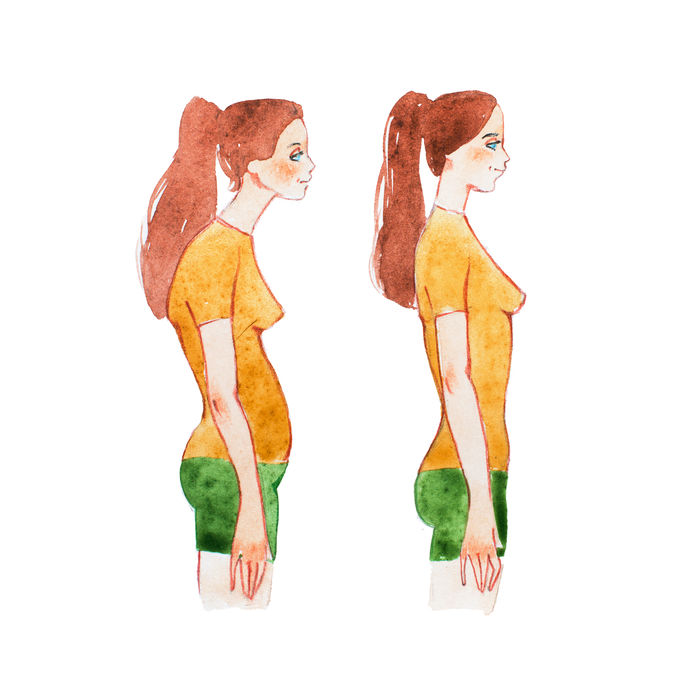

El doblarse hacia delante le llamamos cifosis. Si miramos la columna desde el lado, veremos que tiene unas curvas. Son normales, tenemos el tórax algo redondeado y la columna lumbar algo metida (todos somos un poco “culo pollo”). De este modo hablaremos de una cifosis torácica y de una “lordosis” lumbar. A los padres os preocupa la cifosis, es normal, es lo que se ve. A tu fisio le preocupará más la curva lumbar que tiene que ver en la forma que posicionas tu pelvis y afecta a la “postura global”.

Si no hay enfermedad, se trata de una cifosis flexible que trataremos con ejercicios de potenciar músculos de la espalda o incluso con psicoterapia para los casos que tenga algo que ver con inseguridad o miedo al nuevo aspecto de cuerpo adulto. Hay un truco que os funciona muy bien y que veo que evita conflictos madre-niño. Estáis ambos hartos de decir/escuchar el “ponte recto” o “saca pecho”. En vez de eso vais a recordar lo que os explico en la consulta “gira las manos”. Se trata de girar las manos hacia fuera, mucho, mucho, hasta que los pulgares casi apunten hacia atrás. Eso te hará crujir la espalda y notarás que se pone recta. Memoriza esa posición y guárdala.

Me he dado cuenta que parte de este problema es nuestra cultura de lo estéticamente deseable. El cuerpo quiere tener un tórax con volumen suficiente para los pulmones y corazón. Le da igual si es plano atrás y saliente delante o si es romo por detrás y plano por delante. Pero admitámoslo, nos gusta una espalda recta “de nadador” y un tórax algo saliente como de “estar fuerte”. Mira bien cómo es el tórax de papá o del abuelo. Tal vez el del niño sea como el de la familia, no lo olvides.